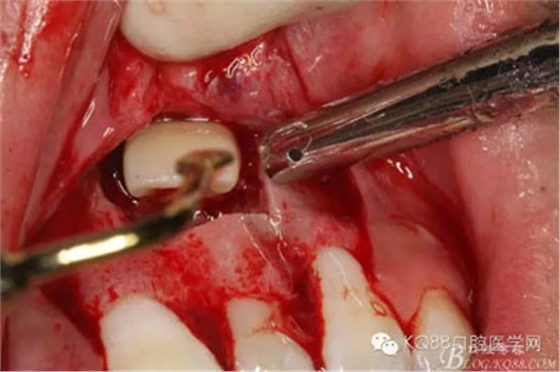

圖11.掀開骨壁。摘除牙瘤及牙囊組織

圖12.摘除囊壁后,暴露出21的切端

圖13.超聲骨刀清理周圍組織,21有Ⅰ°松動